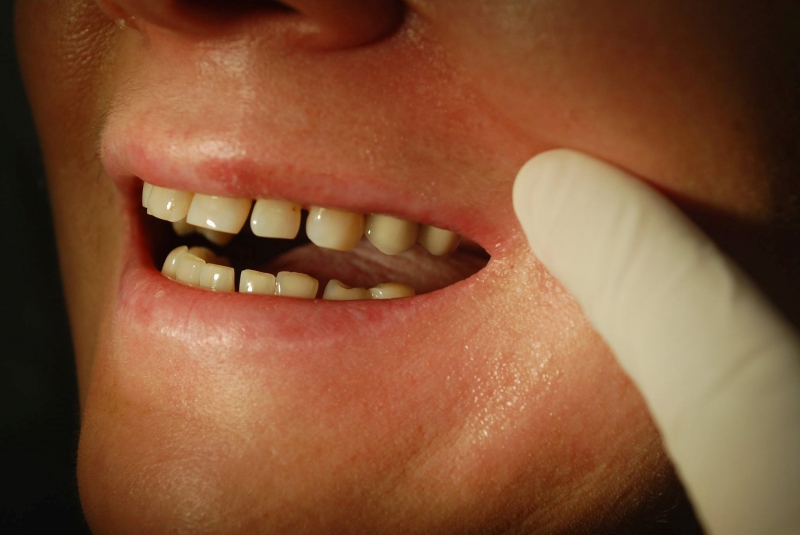

Sólo korunky, nahradené implantátmi